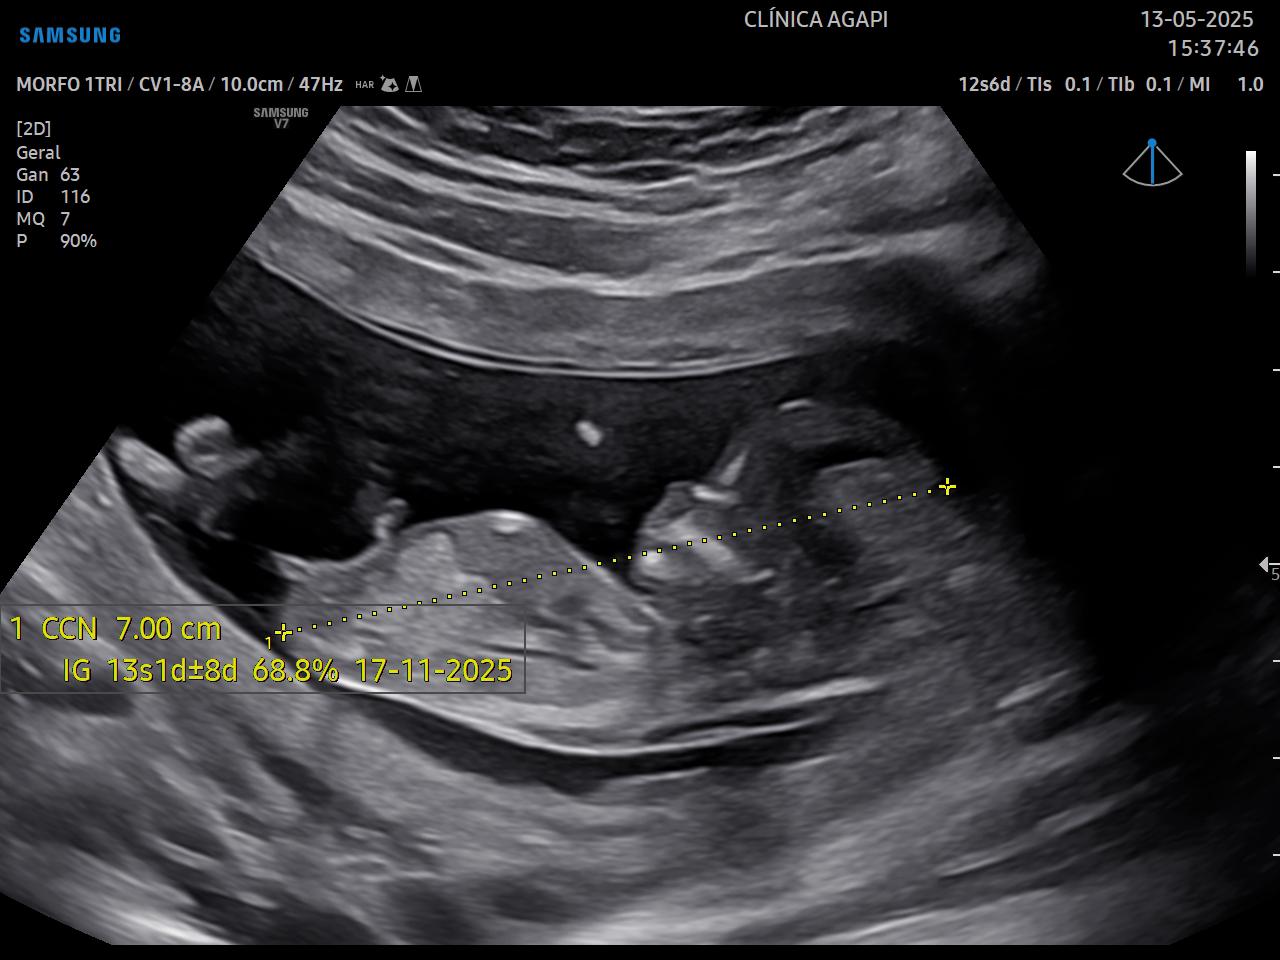

Deve ser realizado entre 11 semanas e 3 dias e 13 semanas e 6 dias, preferencialmente na 12ª semana, pelas vias abdominal e transvaginal.

Seu principal objetivo é avaliar o risco de aneuploidias (doenças genéticas no bebê), avaliar risco da mãe desenvolver pré eclâmpsia, e também avaliar minuciosamente a anatomia do bebê. É possível detectar cerca de 50% das malformações congênitas pela avaliação inicial da anatomia do feto.

O rastreio de aneuploidias é feito através da avaliação de marcadores ultrassonográficos específicos como: transluscência nucal, osso nasal, ducto venoso e regurgitação tricúspide.